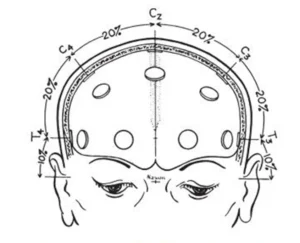

The first measurement is in the anterior-posterior plane through the vertex, taken from the nasion to the inion. This measurement is divided into 5 separate areas (see fig.1).

The first mark is placed at 10% of the total measurement and labeled Fp. The second, third, fourth and fifth marks are placed at 20% intervals of the total measurement and labeled F, C, P, and O. Note that the O mark would be located at 10% of the measurement above the inion. The expression Fp, F, C, P and O represent the fronto polar, frontal, central, parietal and occipital areas, respectively.

Fig.1 Lateral view oof skull to show methods of measurement from nasion to inion at the midline. Fp is frontal pole position, F is the frontal line of electrodes, C is the central line of electrodes, P is the parietal line of electrodes and O is the occipital line. Percentages indicated represent proportions of the measured distance from the nasion to the inion. Note that the central line is 50% of this distance. The frontal pole and occipital electrodes are 10% from the nasion and inion, respectively. Twice this distance, or 20% separates the other lines of electrodes

Fig.2 Frontal view of the skull showing the method of measurement for the central line of electrodes as described in the text.